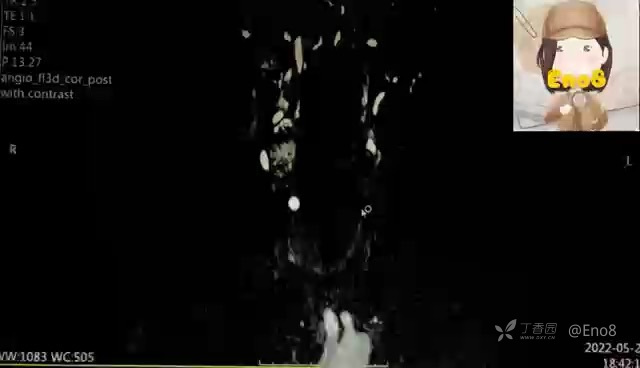

最后放一下该患者的MRI增强

而MRI增强则直接诊断颈动脉体瘤,这与我的诊断完全不符。这个时候,我就开始翻找资料,在复习了相关颈动脉体瘤的超声知识后,才觉得当时的诊断有点想当然,而且即使考虑结核性淋巴结,也没有搞清楚结核性淋巴结的声像图该如何表现,所以就这个病例,跟大家一起再复习一下颈动脉体瘤。

现在回过头来想,该患者颈部两个包块定位均位于颈动脉分叉处,呈实性低回声改变,外形规则,境界尚清,同时二者迫使颈内外动脉夹角增大,呈“高脚杯”征。